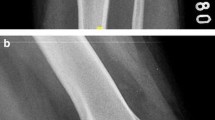

The position and shape of the femoral and tibial tunnels were evaluated by the 3D-CT reconstruction images 1 day after surgery.

No complications, such as posterior femoral tunnel fractures, wound infections, cartilage lesions, difficult graft passage, or neurovascular injuries, occurred in either of the two groups. Two patients in group 1 and five in group 2 presented with redness and swelling of the surgical site and were managed conservatively. One patient in group 2 sustained a tibial tunnel fracture, which was immobilized with plaster and resumed rehabilitation 4 weeks later. One patient in group 1 had postoperative stiffness that later resolved with physiotherapy. There were no re-rupture cases at the last follow-up, as confirmed by the MRI scans. The entrance of the femoral tunnel in both groups was within the ACL anatomical footprint, as confirmed by 3D-CT (Fig. 3).